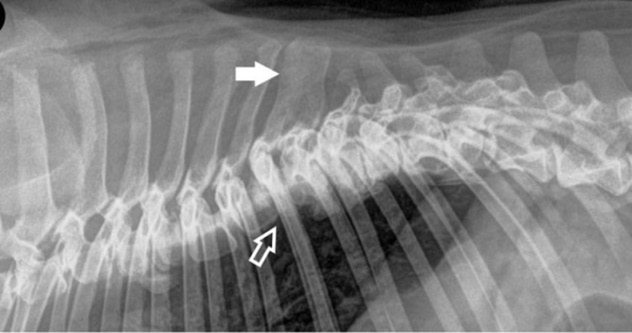

Χαρακτηρίζονται από συνδυασμένη απλασία της κοιλιακής και της μέσης μοίρας του σπονδυλικού σώματος με συνέπεια τη δημιουργία «σπονδύλου δίκην πεταλούδας». Οι σπόνδυλοι αυτοί απεικονίζονται σε ραχιαία προβολή.

Στην ακτινογραφία (ραχιαία προβολή) απεικονίζεται ο σπόνδυλος Θ12 που έχει το σχήμα πεταλούδας